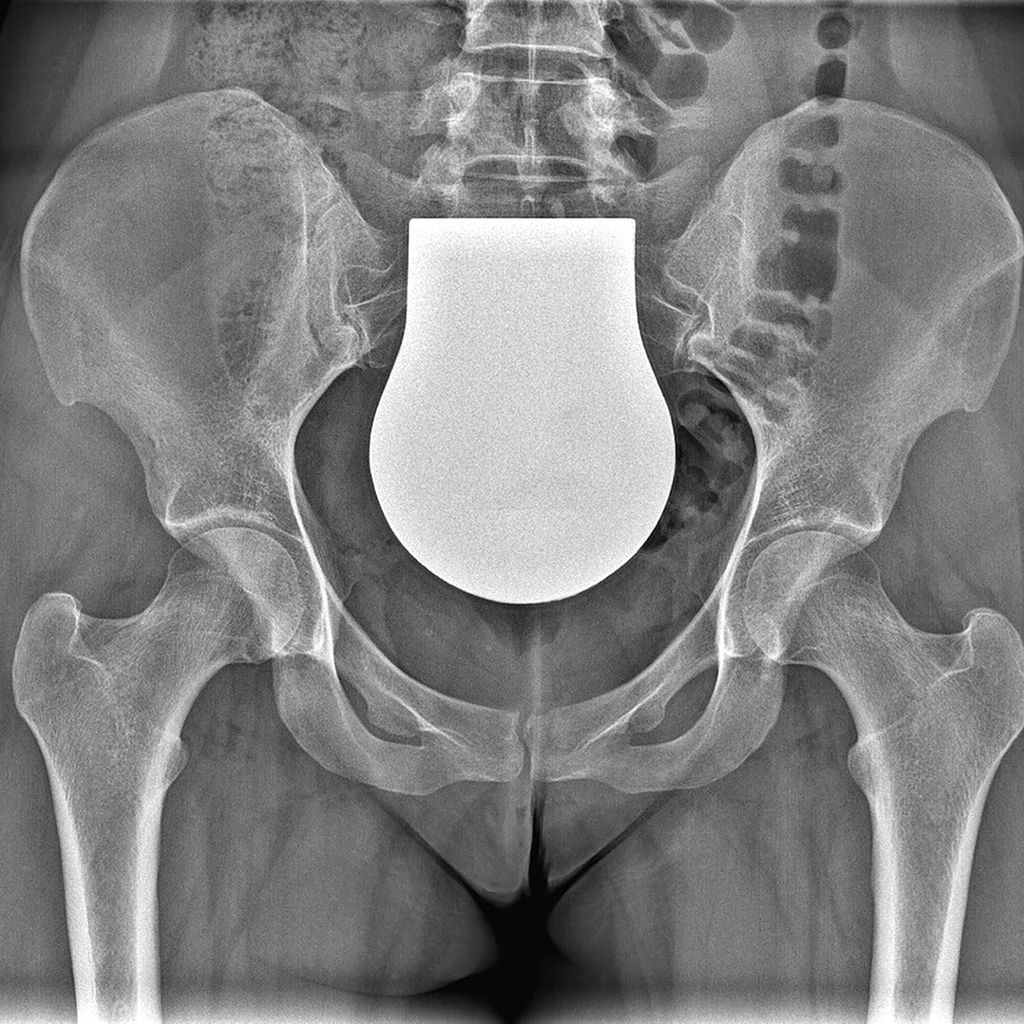

Die periacetabuläre Beckenosteotomie (PAO) nach Ganz hat sich seit der Erstpublikation 19881 zu einem etablierten Verfahren in der rekonstruktiven Beckenchirurgie entwickelt. Bei der PAO wird die Hüftgelenkspfanne chirurgisch ausgeschnitten, um in der Folge vollkommen mobil, mit der Hüftkopfmitte als Drehzentrum, in einer korrigierten Position mit dem Becken neu fixiert zu werden. Das Verfahren erlaubt eine bessere Primärstabilität gegenüber der Triple-Beckenosteotomie, da der hintere Beckenpfeiler nicht durchtrennt wird und die Integrität des Beckenrings somit intakt bleibt. Eine Fixierung der Osteotomie mit Schrauben erlaubt unmittelbar postoperativ eine Übungsstabilität. Eine Gipsruhigstellung wie bei der Triple-Beckenosteotomie ist in der Regel nicht erforderlich. In der Rehabilitationsphase ist eine Gewichtsbelastung der Hüfte in der Regel nach 6 Wochen schrittweise möglich.

Intraoperative Bildgebung als Fehlerquelle hinsichtlich der Pfannenversion

Die intraoperative Reorientierungs-Position des Pfannenfragmentes auf Basis von Durchleuchtungsbildern in liegender Position stellt derzeit immer noch eine große Herausforderung für jeden Chirurgen dar. Die Ursachen dafür liegen einerseits in der posterior-anterioren Röntgenstrahlrichtung und der geringen Film-Fokus-Distanz der intraoperativen Durchleuchtung im Vergleich zur konventionellen Beckenröntgenaufnahme, andererseits in einer veränderten Beckenkippung im Liegen im Vergleich zur stehenden Position. Diese Faktoren verändern die Darstellung der Pfannenversion intraoperativ. Da aber sowohl eine Unter- als auch eine Überkorrektur der Pfannenversion zu klinisch schlechteren Ergebnissen und in der Folge zu einer erhöhten Arthroserate führt, ist auf die Pfannenversion besonders zu achten.5 Die Verwendung von Schnitt- und Korrekturblöcken könnte hier zukünftig Abhilfe schaffen.

Die Verwendung einer patientenspezifischen Instrumentation (PSI) auf Basis einer 3D-Modell-Planung ist bei knienahen Umstellungsosteotomien in der Orthopädie bereits ein gängiges Verfahren. Dieses Konzept kann nun teilweise auch bei der PAO angewendet werden. Dabei wird das knöcherne Becken präoperativ in der Computertomografie erfasst und am 3D-Modell werden die optimalen Schnittführungen um die Hüftgelenkspfanne geplant. Mittels eigener Software kann das Acetabulum am Monitor auf ein Grad genau in allen Ebenen gedreht werden. Auch eine notwendige Translation des Fragments kann beurteilt werden. In der Korrekturposition des Pfannenfragments können zusätzlich bereits die Positionen und Längen der Schrauben errechnet werden. Auf Basis dieser Planung werden PSI-Schnittblöcke und Korrekturblöcke produziert und für den Eingriff sterilisiert.